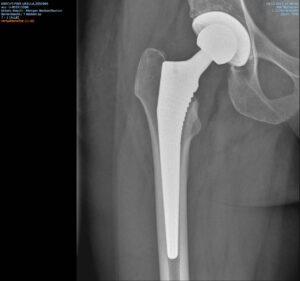

Arthrose- oder Gelenksabnützung stellen ein zunehmendes Problem der immer älter werdenden Bevölkerung dar. Die aktuellen Behandlungsmöglichkeiten erlauben es jedoch Lebensqualität und Aktivität zu erhalten.

Eigenblut- und Stammzellentherapie; durch die Aktivierung des Heilungspotenzials des eigenen Körpers können operative Behandlungen umgangen oder hinausgezögert werden. Erweitern Sie ihr Wissen und vertiefen Sie ihre Fragen am Infostand vor Ort.